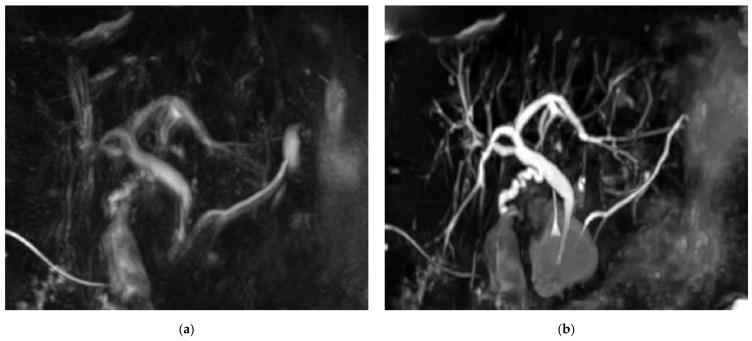

Figure 3 shows example MRCP images obtained with RT-MRCP and CS-BH-MRCP sequences with their qualitative image-quality criteria scorings.